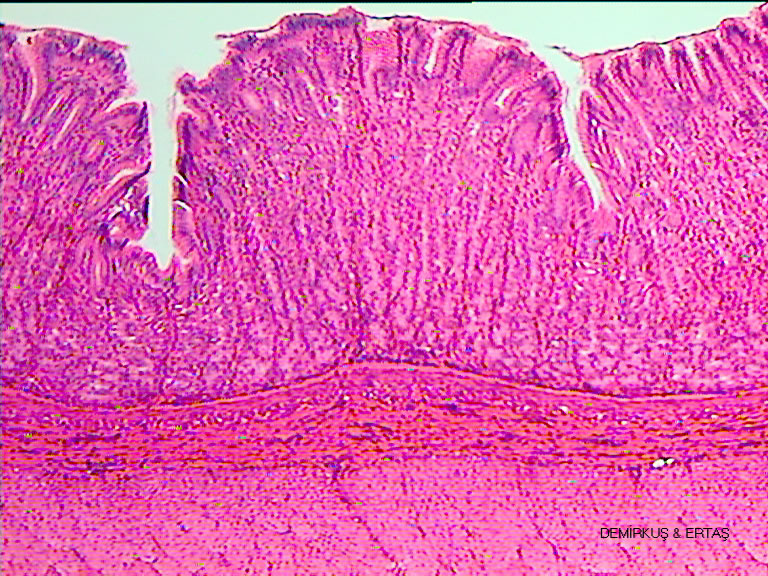

U/Stomach-paries-sec-4.jpg